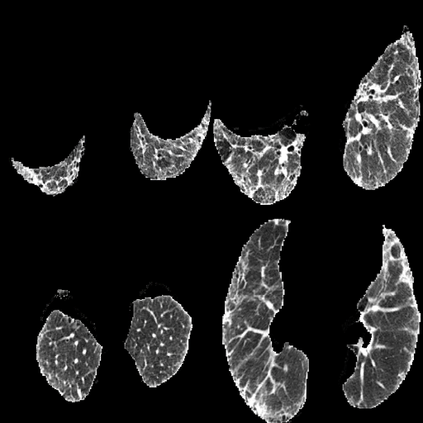

In the field of medical imaging, particularly in tasks related to early disease detection and prognosis, understanding the reasoning behind AI model predictions is imperative for assessing their reliability. Conventional explanation methods encounter challenges in identifying decisive features in medical image classifications, especially when discriminative features are subtle or not immediately evident. To address this limitation, we propose an agent model capable of generating counterfactual images that prompt different decisions when plugged into a black box model. By employing this agent model, we can uncover influential image patterns that impact the black model's final predictions. Through our methodology, we efficiently identify features that influence decisions of the deep black box. We validated our approach in the rigorous domain of medical prognosis tasks, showcasing its efficacy and potential to enhance the reliability of deep learning models in medical image classification compared to existing interpretation methods. The code will be publicly available at https://github.com/ayanglab/DiffExplainer.